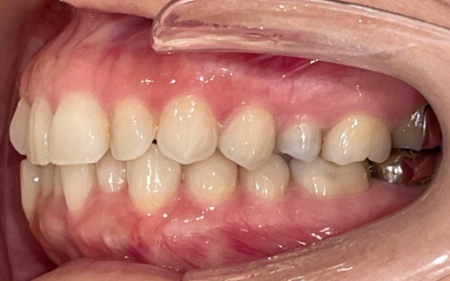

40代女性 マウスピース矯正を使用し前歯の叢生を短期間で整えた症例

拝見したところ、上下の歯並びには歯がずれたりねじれたりして生えている「叢生(そうせい)」が認められました。

特に上下前歯は重なりが目立ち、お口を開けた際の見た目にも影響を与えていました。